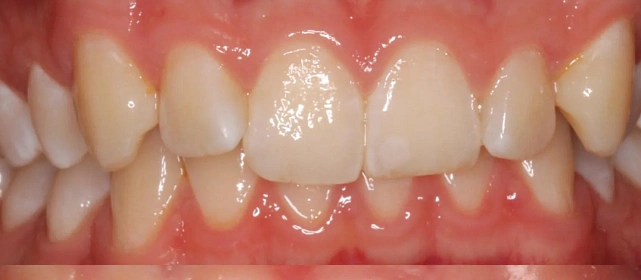

Зубы выровнены, смыкание нормализовано. Установлены несъёмные ретейнеры на обе челюсти. Пациент направлен к ортопеду.

Решение: Поставили элайнеры Invisalign на обе челюсти. Лечение заняло 4 года — случай потребовал нескольких этапов коррекции, каждый из которых последовательно приближал зубы к нужному положению. Капы менялись каждые 1–2 недели, контрольные визиты — для отслеживания прогресса и выдачи новых наборов. Зубы встали на место, смыкание пришло в норму. Зафиксировали ретейнеры на обе челюсти, пациент направлен к ортопеду для завершающего этапа.

Случай потребовал нескольких последовательных этапов коррекции. Invisalign позволяет дозаказывать капы в рамках лечения, и здесь это понадобилось — каждый следующий этап доводил положение зубов точнее. Результат достигнут, прикус стабилен, ретейнеры на месте. Пациента направила к ортопеду.